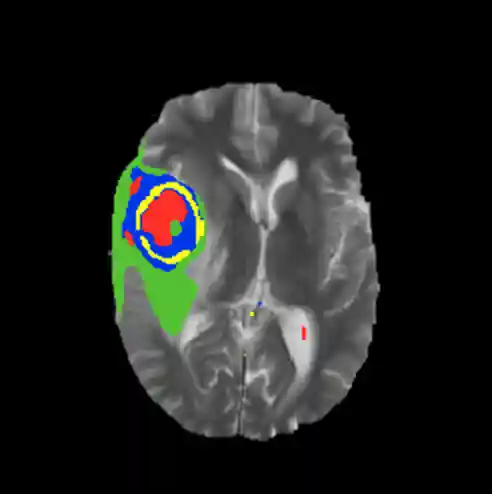

Below is a summary of how well the current model is predicting. As more advances are made this section will be updated. A representative example of a tumor segmentation on test data is displayed in Figure 10. The model can identify each of the four classes with a good amount of accuracy, with the exception of class boundaries, which are smoother in my prediction than the ground truth.

Figure 10: Results of CNN model segmentation on a single slice (top) with respect to the ground truth, and a 3D representation of the segmentation (bottom).Notice that towards the top of the 3-dimensional network results representation some of the cerebrospinal fluid (CSF) is incorrectly classified as tumor. This is unsurprising, considering that the CSF has similar features to parts of the tumor in some pulse sequences. There are several potential solutions for this:

- Pre-process the images by masking CSF (much easier than tumors to extract)

- Train the model on more CSF-containing patches so it can learn to distinguish between CSF and tumor

- Add more nodes to the model, which may cause it to learn more features from the current patches.